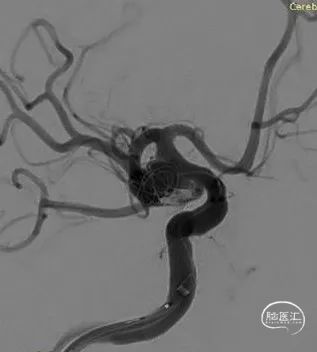

DSA结果:颈内动脉-后交通动脉瘤,动脉瘤大小约9.57*9.71*8.42mm。

术前影像

DSA结果:动脉瘤大,瘤颈较宽,颈内动脉和后交通动脉为瘤颈部分,胚胎后交通动脉,后交通动脉和颈内动脉呈近360°夹角。

颈内动脉-后交通动脉瘤,动脉瘤大小约9.57*9.71*8.42mm,ICA AN近端直径:2.87mm,远端 4.21mm,PCOM直径:1.92mm。